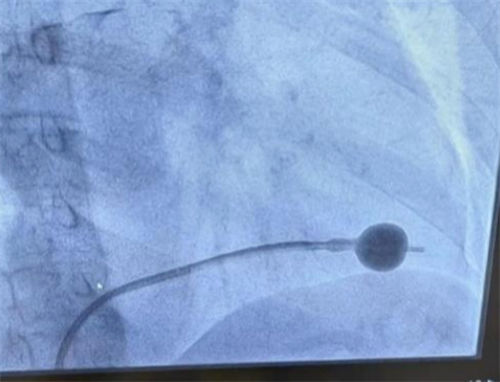

9月18日,北大醫(yī)院太原醫(yī)院(太原市中心醫(yī)院)心內(nèi)科在北大醫(yī)院結(jié)構(gòu)性心臟病專家馬為主任的指導(dǎo)下,成功實(shí)施二尖瓣狹窄球囊擴(kuò)張成形術(shù),填補(bǔ)了心內(nèi)科在此項(xiàng)技術(shù)上的空白,充分體現(xiàn)太原醫(yī)院在心血管介入治療方面豐富的臨床經(jīng)驗(yàn)和過硬的技術(shù)實(shí)力。此次來院,馬為主任還完成了三臺(tái)先天性心臟病介入手術(shù)(房間隔缺損封堵術(shù))。

68歲的陳阿姨因間斷胸憋、心前區(qū)不適17年,加重伴活動(dòng)后心悸、氣短1月余入院。入院診斷為風(fēng)濕性心臟病,二尖瓣狹窄(中-重度)伴關(guān)閉不全(輕-中度)。此類患者藥物保守治療效果較差,而外科手術(shù)不僅需要承擔(dān)高昂的手術(shù)費(fèi)用,且手術(shù)創(chuàng)傷大、恢復(fù)時(shí)間長(zhǎng),讓多數(shù)患者心里打起退堂鼓。

醫(yī)療技術(shù)平移,讓山西人民在家門口即可真正享有“國(guó)家隊(duì)”水平的優(yōu)質(zhì)醫(yī)療服務(wù)。馬為主任認(rèn)真分析病情并迅速確定手術(shù)方案。在馬為主任的指導(dǎo)下,陳阿姨整個(gè)手術(shù)過程銜接有序、行云流水、一氣呵成,僅僅歷時(shí)90分鐘,出血量10毫升。術(shù)后,患者自述胸憋、氣緊癥狀明顯減輕,聽診患者二尖瓣聽診區(qū)雜音完全消失。

傳統(tǒng)治療是全麻下外科開胸手術(shù)行二尖瓣置換手術(shù),手術(shù)創(chuàng)傷相對(duì)較大。而二尖瓣球囊擴(kuò)張成形術(shù)是不同于外科開胸手術(shù)的介入微創(chuàng)治療方法。